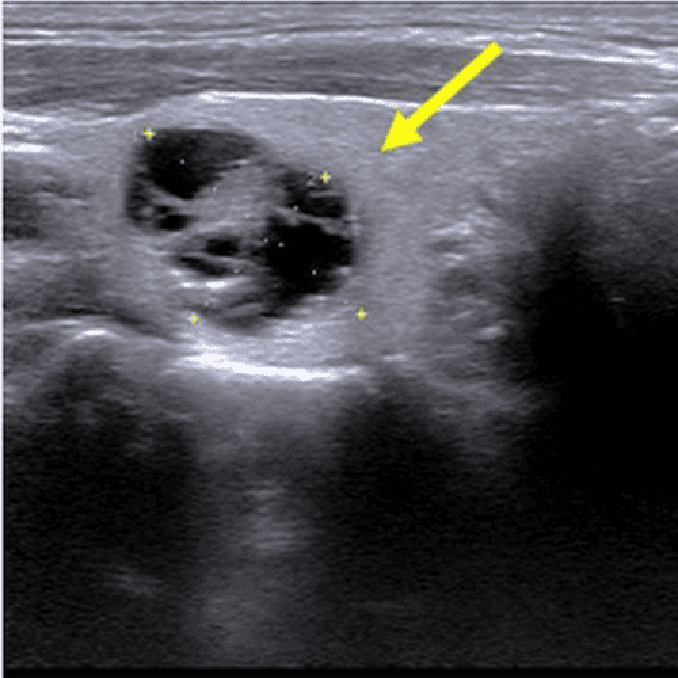

Sol tiroid lobunda 11 mm çaplı papiller karsinomu olan 59 yaşındaki kadın hastamıza perkütan kriyoablasyon uygulandı. Dokuz ay sonra, nodül ultrasonda görülememiş ve 1.5 yıllık takip boyunca hastada herhangi bir nüks olmamıştır.